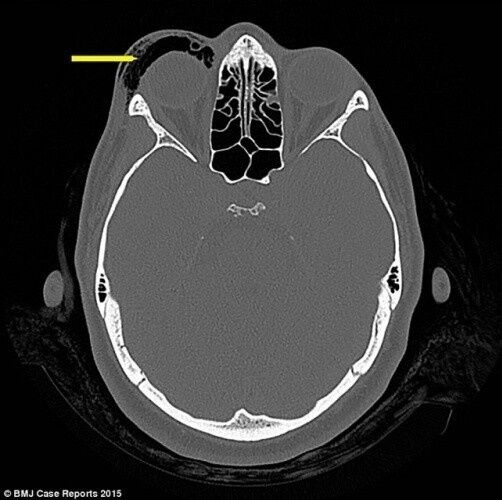

32 yaşındaki kadını hızlıca burnunu sildikten sonra gözü golf topu büyüklüğünde şişince doktorlar bile şok oldu.

Bu tür yaralanmaların normalde patlamalar sonrasında yaşandığı belirtildi. Doktorlar kadını ivediklikle tedavi ederken, tedavi edilmemesi durumunda körlük yaşanabileceğine dikkat çekti.

Bölgede oluşan basınç optik sinirlere hasar verebiliyor. Benzeri vakalarda hemen doktora başvurulması gerektiği dile getirildi.